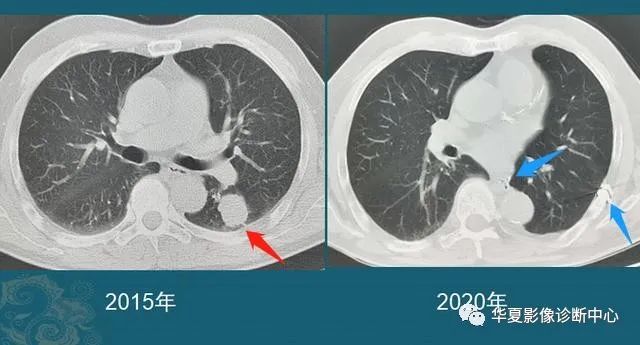

豪大夫每年都能发现很多从肺小结节长大的肺癌,挑出两个速度最快的分享一下:

图6

这位病人2016年体检还是正常的,2017年查出一个3 mm的肺结节,用了两年半时间,增长到>1 cm,手术病理是肺腺癌。

注意:这几乎是最快的一类的,很少见!所以高危人群推荐每年胸部体检一次是有益的。

图7

这是一位老年男性,有吸烟史,也是在两年多的时间内,肺结节从不足3 mm长到1 cm以上,后来病理确诊肺鳞癌。